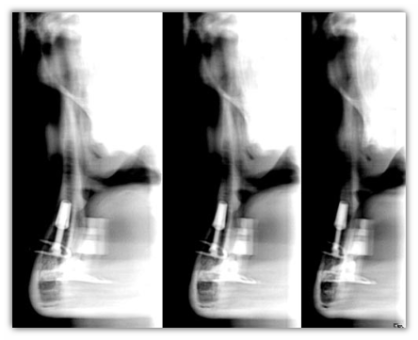

Trophy Radiologie panoramico digitale TrophyPan

TrophyPan

L'ortopantomografo totalmente digitale.

TrophyPan e completamente ed esclusivamente digitale e risulta l'espressione di tutti i vantaggi offerti da questa tecnologia. L'immagine viene trasmessa al personal computer in tempo reale durante la rotazione della testa e si completa in circa 15 secondi, senza tempi di attesa e senza tutti i problemi relativi allo sviluppo.